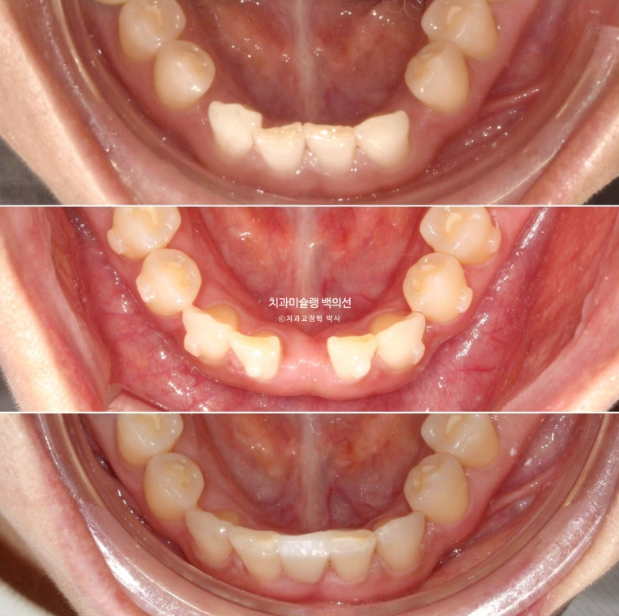

교정치료를 위해 내원한 환자분입니다. 아래 앞니 두 개가 없어서 이 사이 벌어짐을 치료하고자 오셨습니다.

윗니가 아랫니를 깊게 덮는 과개교합도 보입니다.

사진에 보이는 구멍은 앞니가 없어 송곳니가 앞니 자리로 이동하고 송곳니와 작은어금니 사이 공간이 벌어져 있습니다.

송곳니가 없는 것 처럼 보이지만 사실은 앞니 2개가 선천적으로 없는 상태입니다.